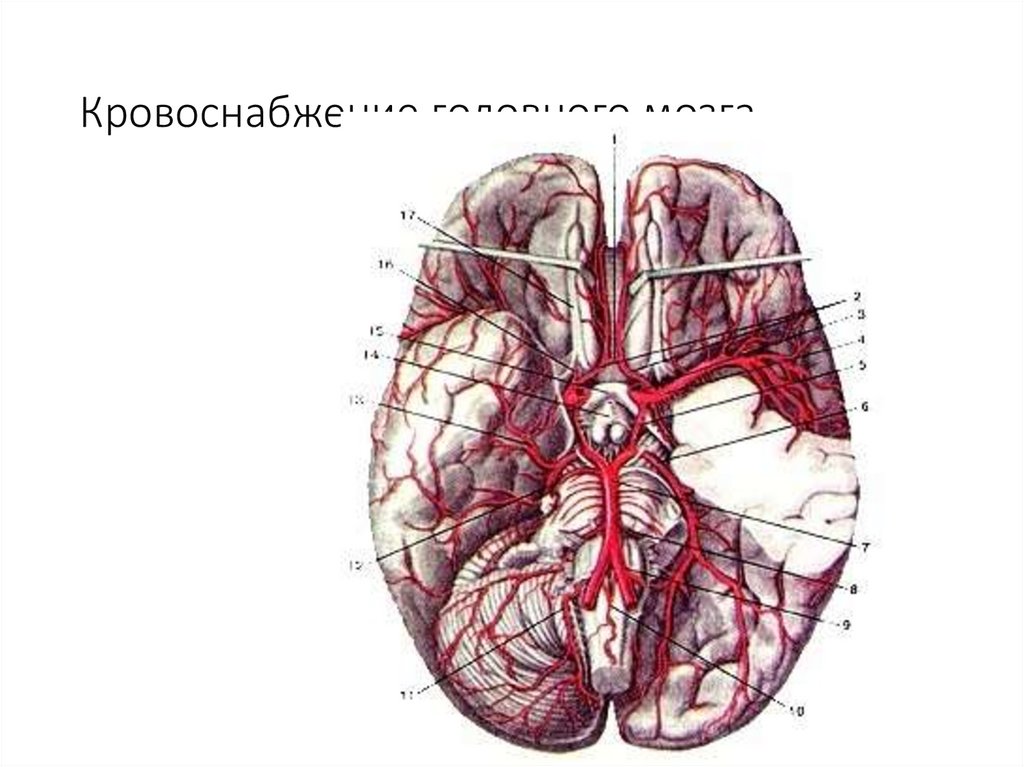

Кровоснабжение головного мозга

38. Кровоснабжение головного мозга